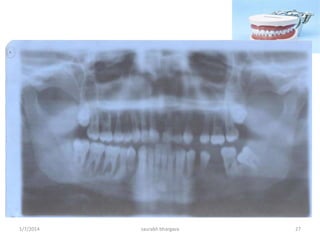

Showing the presence of unerupted

permanent dentition